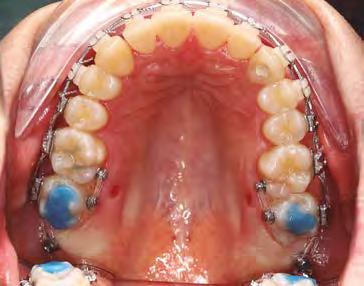

–Corticotomías y Ortodoncia. Ampliando límites del movimiento dental, por la Dra. Aranzazu Senosiain y cols. [50]

–Tratamiento de un caso de Ortodoncia y Cirugía Ortognática con placas preformadas y tecnología 3D, por la Dra. Elena Bonilla Morente y cols. [62]

–Uso del anclaje esqueletal como alternativa eficiente en el manejo ortopédico de clases III por deficiencia de maxilar superior, por el Dr. Carlos Becerra y cols. [74]

–MARPE, una alternativa a la disyunción en el paciente adulto, por el Dr. Enrique Solano y cols. [88]

Ortodoncia interdisciplinar, un enfoque colaborativo para el tratamiento integral de maloclusiones

Protocolo Di gitalArch®️ 2.0: técnica de colocación, por el Dr. Luis Cuadrado Canals y cols.